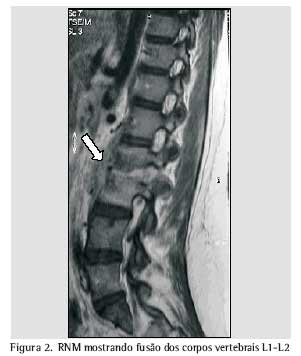

Através da tomografia computadorizada, foram evidenciadas irregularidade e redução do espaço articular entre L2 e L3, associadas à esclerose dos corpos vertebrais correspondentes, e fratura em L2. O disco vertebral entre L5 e S1 apresentava leve protrusão, sem causar repercussões intra-raquianas significativas. Os achados sugeriram a possibilidade de processo inflamatório e/ou infeccioso, acometendo os corpos vertebrais L2 e L3, bem como o disco intersomático correspondente (Figura 1). A ressonância nuclear magnética evidenciou redução do espaço discal L2/L3 e abscesso frio na área correspondente, o que reforçou a possibilidade de processo do tipo espondilodiscite (Figuras 2 e 3).

A ressonância magnética é o método de imagem mais sensível e mais específico na diferenciação da natureza dos colapsos vertebrais, além de mostrar alterações precoces(9,18,19) para o diagnóstico de espondilite por tuberculose(20), apesar de poder encontrar imagens semelhantes por germes piogênicos e neoplasia vertebral(9, 21).

A redução do espaço intervertebral é atípica( 20, 22) em infecções piogênicas. Porém, as imagens apresentadas por esta paciente, de redução intervertebral associada ao envolvimento de vértebras consecutivas, são consideradas características de espondilite tuberculosa(9).